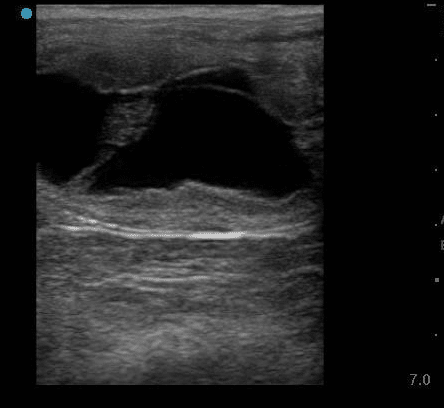

An eight-year-old Tennessee Walker mare is presented for evaluation. She was accidentally turned out with a stallion a couple of times about three or four weeks ago. Transrectal ultrasound of the uterus reveals the following.

What can the owner be told?